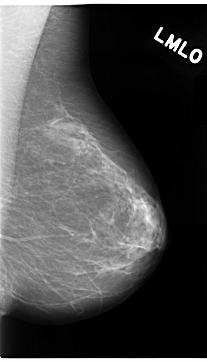

C_0096_1.LEFT_MLO

LEFT_MLO LINES 4704 PIXELS_PER_LINE 2680 BITS_PER_PIXEL 12 RESOLUTION 50 NON_OVERLAY